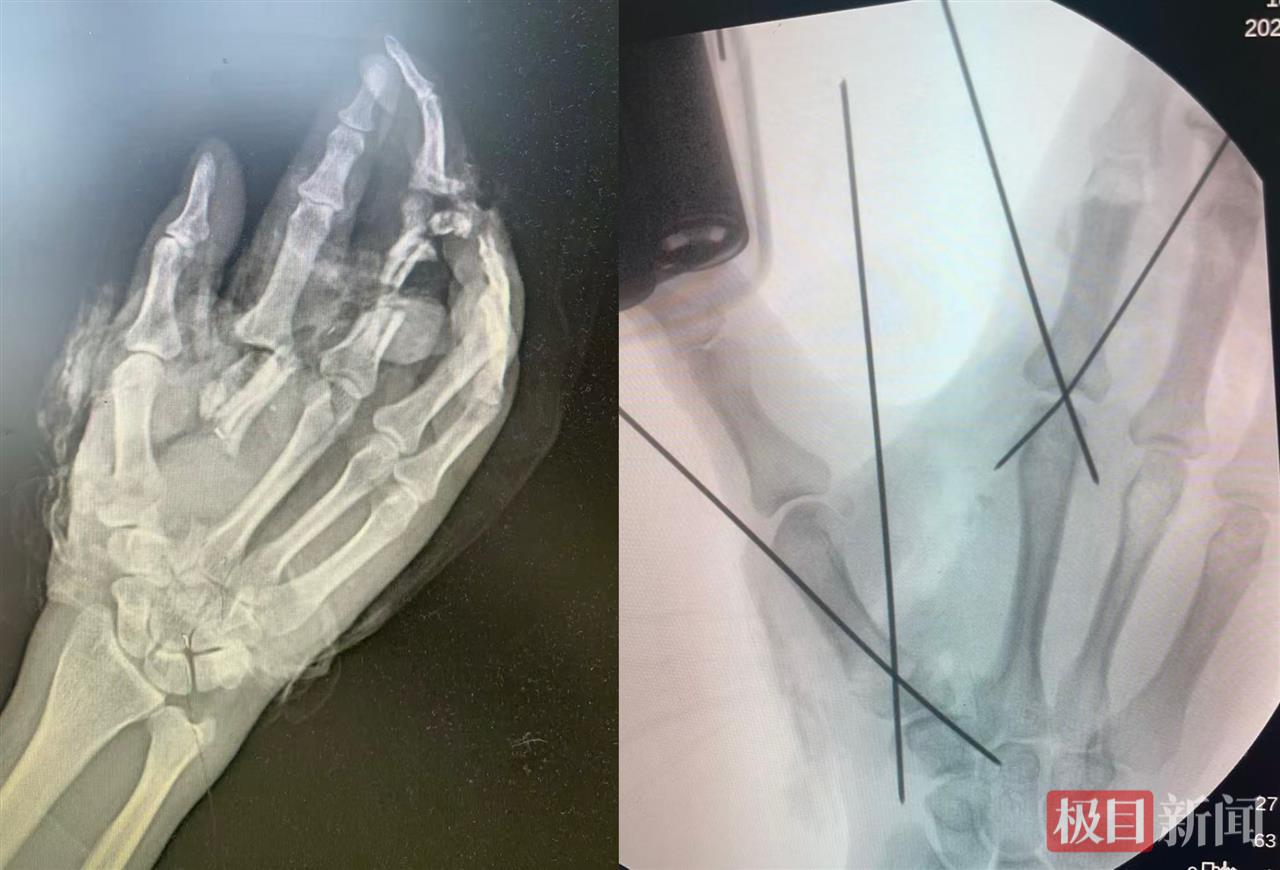

患者手术前后影像图对比

10月底的一个周末下午4时许,陈焱在病区值班时突然接到急诊通知,一位男性工人右手被机器绞伤,手掌及多指离断,情况危机。“患者做工时戴着手套,来的时候右手也是被包着的,但血流不止,急诊通过X光片初步探查了受伤情况。”陈焱回忆,X光片显示孙先生右手第1、2掌骨及中指粉碎性骨折,可见明显的骨质缺损和大小不一的多块游离骨块。

“纱布拆开清创后,实际伤情比X线片严重得多。”陈焱坦言,孙先生右手掌被从中间绞成两半,5根指头仅有小指完好,拇指从手掌基底部断裂,食指相连的掌骨被“锯飞”成多段,神经血管完全毁损,中指完全毁损,无名指末节骨折外露,远端不翼而飞。“骨头、血管、神经和手掌的肌肉缺的缺,烂的烂,就像绞成了一锅粥。”陈焱说。

“把完好的部分‘挪位置’!”陈焱当机立断,将尚且完整的食指指体转位到中指对应的掌骨上以替代已经毁损的中指,拇指原位再植。同时做虎口成形术,让已经移位的食指能够继续承担他本应有的功能并最大限度保留手掌的外形及抓握力。

显微镜下的操作堪称绣花功夫:拇指需吻合2根神经、1根血管、1根肌腱;移位的食指要和中指对应的关节相固定,神经血管和肌腱相对接;虎口处从患者自身受损组织中修剪皮瓣,旋转缝合以维持手掌开合度,留住右手抓握功能。“手部的神经和血管比笔尖还细,在吻合神经与血管的同时还要将破碎的手掌修剪缝合成原始的模样。”陈焱和张明医师全程仅靠患者残留的组织就地取材完成了手术,最大限度保留了患肢的外观和功能。

当晚10时多,手术结束。术后一周,孙先生的右手拇指、移位后的食指和剩余的2个指体均保持红润饱满,无任何坏死迹象。